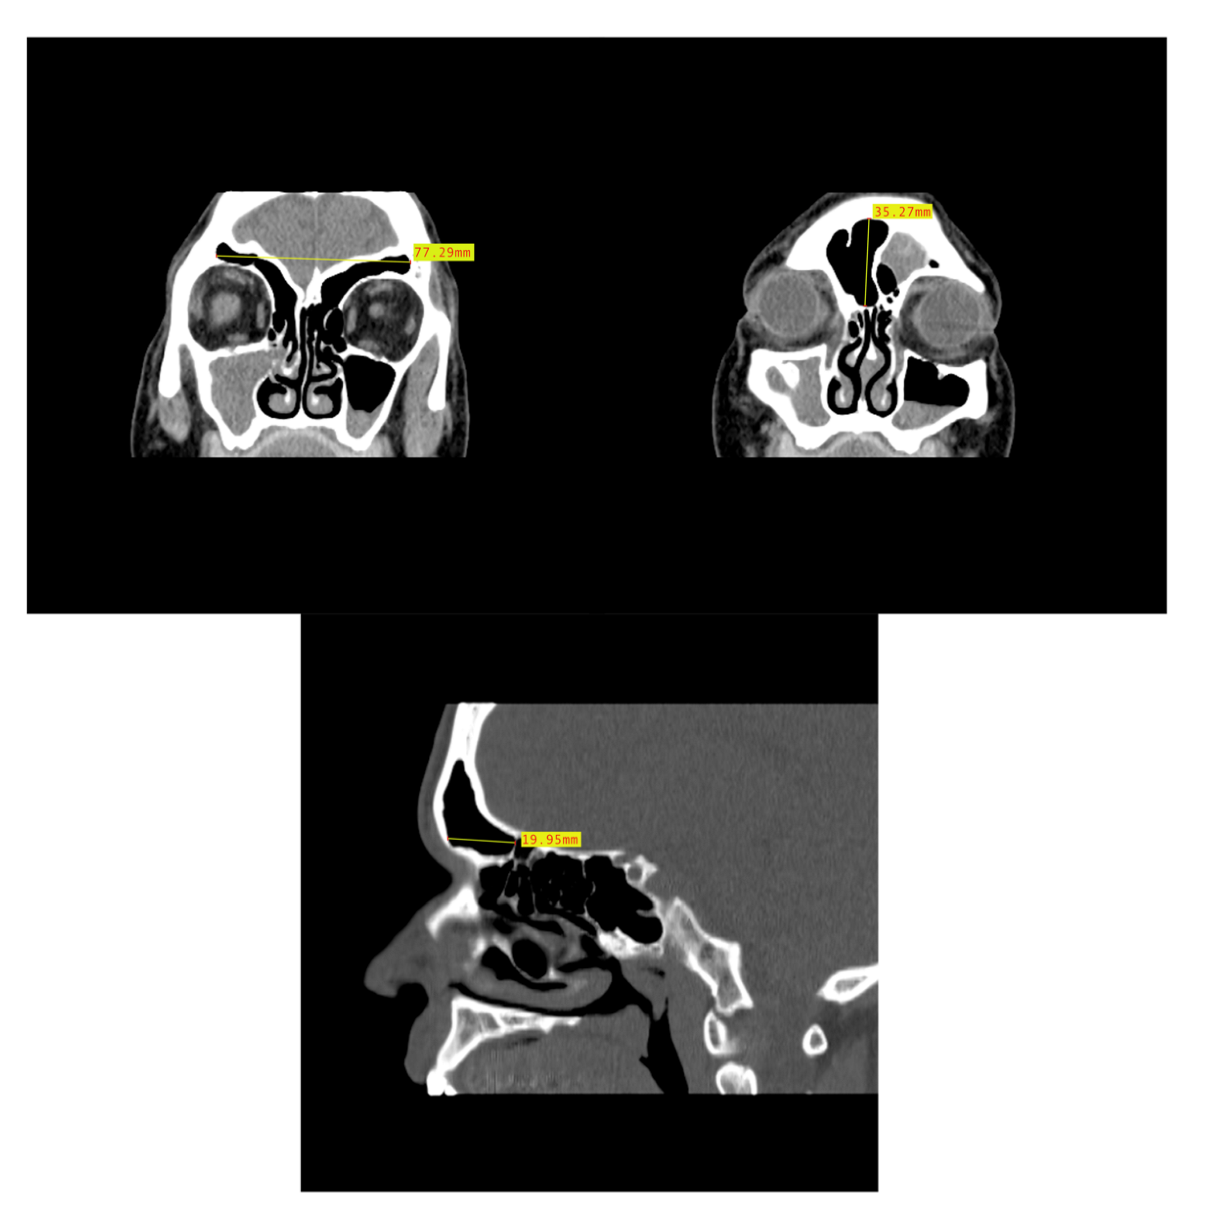

2.2. Dimensional Analysis

3.2. Dimensional Variation Analysis